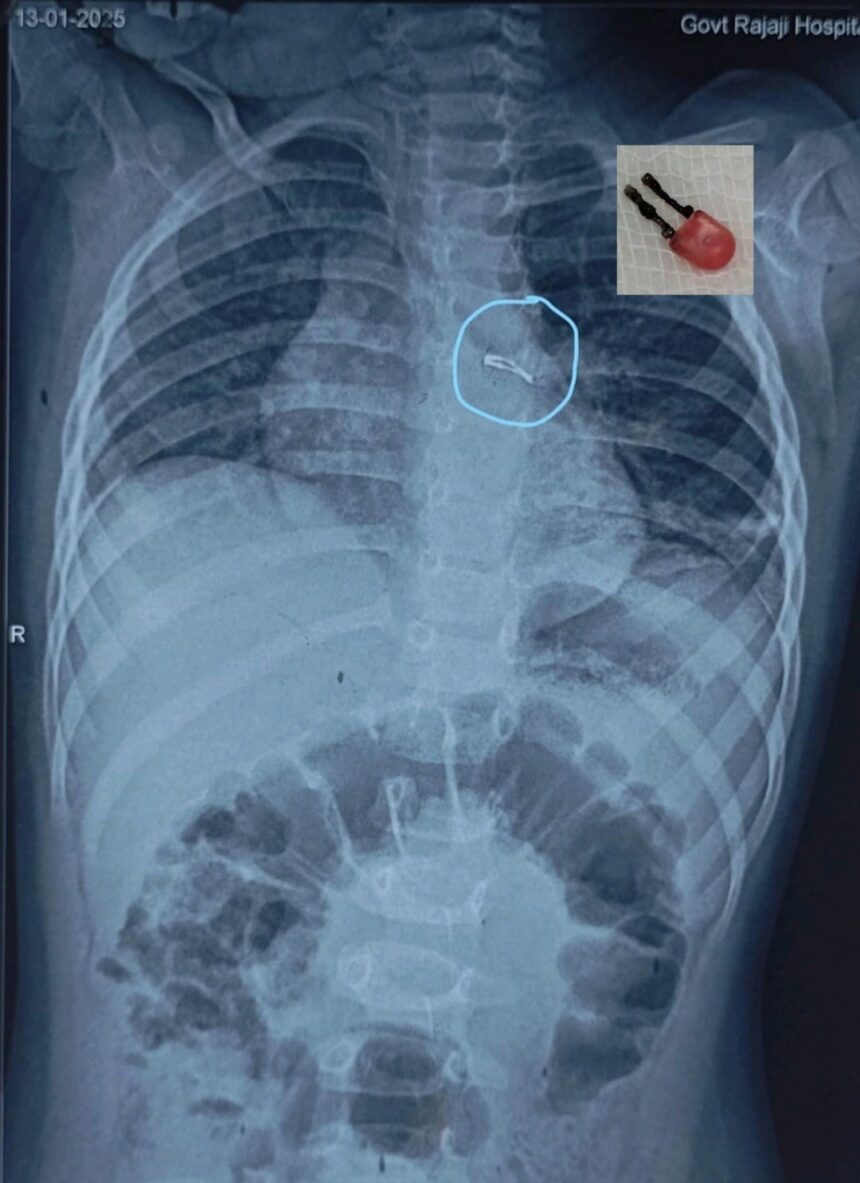

மதுரை அரசு இராசாசி மருத்துவமனையில் கடந்த 13.01.2025 அன்று ஒரு வயது பெண் குழந்தை சுமார் ஏழு நாட்களாக தொடர் இருமல் மற்றும் காய்ச்சலுக்காக உள் நோயாளியாக அனுமதிக்கப்பட்டார். அக்குழந்தையின் பெற்றோர் குழந்தை எந்த பொருளையும் விழுங்க வில்லை என்றனர். அக்குழந்தையின் எக்ஸ்ரே மற்றும் சி.டி.ஸ்கேன் பரிசோதனையில் ஊக்கு மாதிரியான புறப்பொருள் (Foreign Body) மூச்சுக் குழாயின் இடது புறத்தில் கண்டறியப்பட்டது. அரசு இராசாசி மருத்துவமனையின் மயக்க வியல் துறை இயக்குநர் பேராசிரியர். மரு.கல்யாணசுந்தரம் தலைமையிலான மயக்க வியல் மருத்துவ குழு மற்றும் நெஞ்சக நோய் மருத்துவ துறைத் தலைவர் பேராசிரியர் மரு.பிரபாகரன் மற்றும் குழந்தைகள் அறுவை சிகிச்சை துறைத் தலைவர் பேராசிரியர் மரு.மீனாட்சி சுந்தரி உள்ளிட்ட மருத்துவ குழுவினர்கள் 16.01.2025 அன்று மூச்சு குழாய் உள்நோக்கி பரிசோதனை கருவி கொண்டு பரிசோதித்ததில் LED ல் இருப்பது கண்டறியப்பட்டு சுமார் இரண்டு மணி நேர தீவிர முயற்சிக்குப் பின் வெற்றிகரமாக நீக்கப்பட்டது. இந்த சிகிச்சைக்குப் பிந்தைய தீவிர மருத்துவ கண்காணிப்பில் குழந்தையின் உடல்நிலை சீராக உள்ளது